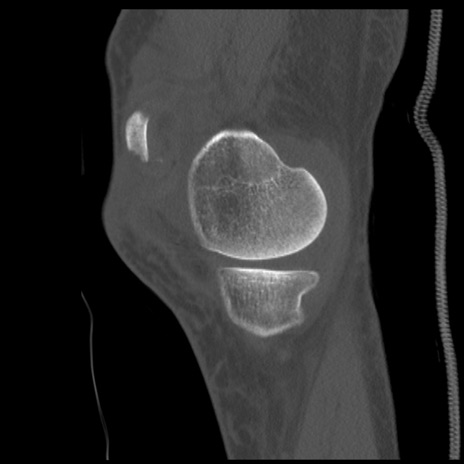

症例28 右膝関節CT(矢状断像)

右膝関節CT